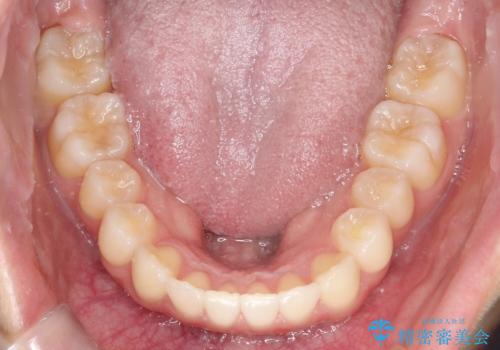

初診時の歯並びの状態としては、上下ともに全体に及ぶの中等度のがたつき(叢生)があり、全特に左上の前歯は1本だけ引っ込んでいる状態でした。

抜歯は行わず上顎の奥のスペースを利用して歯をスライドする方法の他に歯列弓の拡大やディスキング(歯と歯の間の隙間を作る処置)を行い叢生を改善しました。